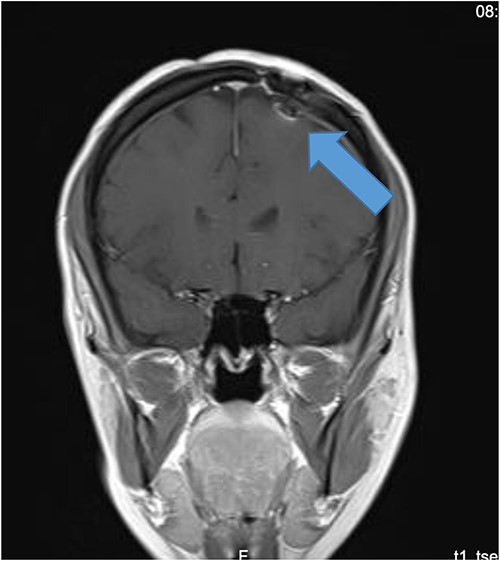

Our patient is a 31-year-old female who presented to the emergency department due to two episodes of generalized tonic colonic seizures. Upon presentation, the patient was administered with supplemental oxygen. She was drowsy and confused while exhibiting signs of right-sided hemiparesis and paralysis. Her pupils were 3 mm and reacted briskly while she showed good left-sided localizing. Her seizures terminated after intravenous administration of midazolam at 5 mg. Further, it was known that she has been symptomatic for 1 month and had been suffering from episodes of seizures, with shaking and tremors of upper limbs, and brief episodes of blackouts for about a minute. These episodes were associated with headache and nausea but were self-limited. Seizures recurred two to three times per week. She denied any fall, tongue bite, loss of consciousness, and limb weakness or numbness. A computerized tomography (CT) scan was suggested, which showed left high parietal hypodensity with vasogenic edema (Fig. 1). She was recommended Keppra 1.5 g and dexamethasone 12 mg. Further, a contrast MRI of the brain was performed (Fig. 2). After a thorough evaluation of the patient’s medical records and current condition, it was decided to proceed with an excision of the tumor using the AC technique. To foster trust and comfort, the same anesthesia and surgical teams were assigned to the patient. Before the procedure, the patient was fully informed about the nature of the procedure and the possibility of a failed outcome or further need for a conversion to general anesthesia. To assess the patient’s cognitive and language abilities, preagreed questions and exercises were performed. These included memory-related queries, such as asking for the patient’s phone number and the names of her dog, and motor commands, such as squeezing a squeaky toy. The patient was prepared for awake navigator-assisted left frontal craniotomy for excision of the left frontal lobe space-occupying lesion, which was suspected to be either a low-grade glioma or fibrous dysplasia. During the surgical procedure, a central line was placed in the right jugular vein using ultrasound, followed by the insertion of a right radial arterial line, a urinary catheter, and two additional venous lines. The patient received a continuous flow of 4–6 l of oxygen per minute. To achieve conscious sedation, the patient received infusions of remifentanil and propofol at varying rates. The patient underwent a 5-hour surgical procedure to remove a tumor. During the procedure, the patient was under sedation and was regularly tested for response to predetermined commands. Her conscious sedation level fluctuated, but she never lost consciousness. The removal of the tumor was successful, and postoperative examination revealed normal motor function and cranial nerve function. The patient was taken to the intensive care unit, and postoperative MRI showed a reduction in the size of the mass lesion in the left frontal lobe/superior frontal gyrus along with mild vasogenic edema surrounding it (Fig. 3).

MRI brain with contrast (A) T2, (B) FLAIR, and (C) T1 postcontrast; in comparison to the fore mentioned study; still noted postoperative changes in the form of craniotomy (regression of size of space occupying cortical mass lesion with mild surrounding vasogenic edema in the left frontal lobe/superior frontal gyrus).